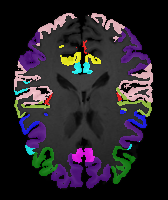

Brain MRI experiment: We also evaluate our method on the MindBooggle101 [4] brain MRIs with 32 cortical regions. We fuse corresponding segmentation labels of the left and right brain hemispheres. MindBoogle101 consists of images from multiple datasets, e.g., OASIS-TRT-20, MMRR-21 and HLN-12. After removing images with incorrect labels, we obtain a total of 85 images. We use 5 images from OASIS-TRT-20 as validation set and 15 as test set. We use the remaining 65 images for training. Manual segmentations in the N=1 and N=21 experiments are only from the MMRR-21 subset; this simulates a common practical use case, where we only have few manual segmentations for one dataset and additional unlabeled images from other datasets, but desire to process a different, new dataset. All images are 1mm isotropic, affinely-aligned, histogram-matched, and cropped to size . We apply sagittal flipping for training data augmentation. We use the same loss weights as for the knee MRI experiment except for , since cross-subject brain registrations require large deformations and hence less regularization.

Results: All trained networks are evaluated using Dice overlap scores between predictions and the manual segmentations for the segmentation network, or between the warped moving segmentations and the target segmentations for the registration network. Tabs. 1 and 2 show results for the knee and brain MRI experiments respectively in Dice scores (%). Fig. 2 shows examples of knee MRI registrations and brain MRI segmentations.

Brain results: Dice scores for segmentation and registration increase by about 2.6 and 3.5 respectively for the cortical structures of the brain MRIs.

Qualitative results: DA achieves more anatomically consistent registrations than the mono-networks on the knee (Fig. 2) and Brain MRI samples (see supplementary material).